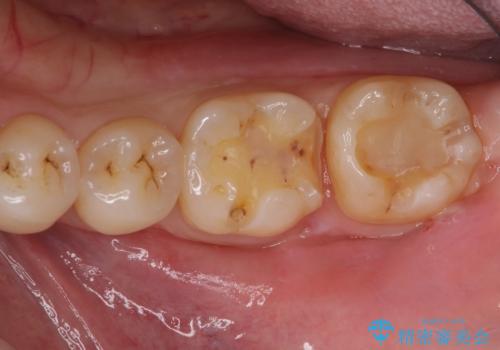

- 左下の銀歯の横から小さい虫歯になっていたため治療しました。